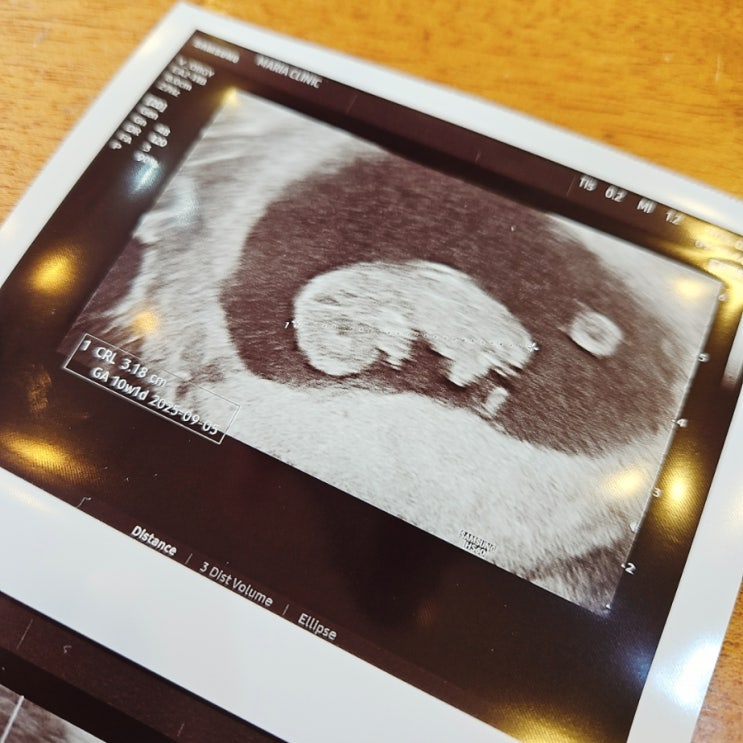

평촌 마리아 졸업 : 임신 9주6일차 초음파, 김안나 선생님께 무한 감사♥

평촌 마리아 졸업 : 임신 9주6일차 초음파, 김안나 선생님께 무한 감사♥ 드디어~!! 평촌마리아 졸업하는 ...